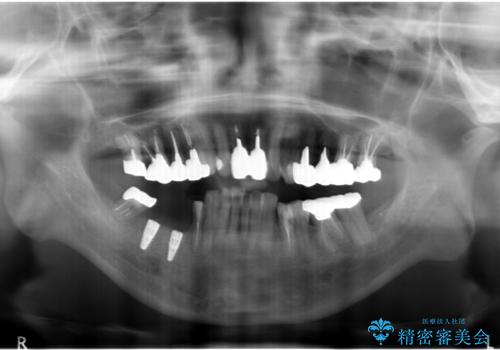

骨が薄いため、他院ではインプラントできないと言われたとの事でした。

精査したところ、右下4の根尖病変及び右下5の欠損を認め、右下6は残根となり保存不可能な状態でした。

保存不可能な歯を抜去後、インプラント治療と根管治療を行いました。

他にも予後不良な歯があり治療を提案しましたが、ご予算もありご希望されませんでした。

インプラントへの悪影響に関しても説明し、了承頂いた上で治療を行いました。

- ¥1,177,000 (根管治療、土台、骨増生、インプラント・アバットメント×2本、仮歯・クラウン×3本) ※税込費用は治療当時の料金となります